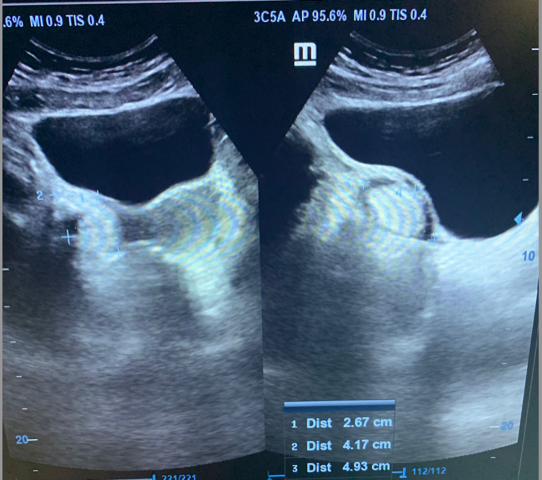

1. Mujer de 62 años; distensión abdominal; carcinoma de ovario.

2. Mujer de 46 años; dolor abdominal; masa ovárica a estudio.

3. Mujer 19 años; asintomática, ecografía durante curso de formación; hamartoma.

4. Mujer 32 años; dolor abdominal; quiste ovárico simple.

5. Mujer 27 años; ITU de repetición; ovario poliquístico.